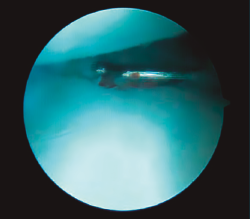

En cuanto al diagnóstico, la controversia reside en cuándo y qué pruebas complementarias realizar en las sospechas clínicas de fractura sin una imagen de radiología concluyente. A menudo las fracturas agudas pasan desapercibidas; la sensibilidad de la radiología va del 84 al 98%(1), la resonancia magnética nuclear (RMN) puede ser útil, con una sensibilidad superior al 95%, pero con una especificidad inferior(2), siendo la tomografía computarizada (TC) la más sensible y especifica(3)(Figura 1).

Figura 1. Imagen de fractura no desplazada de escafoides en tomografía computarizada.